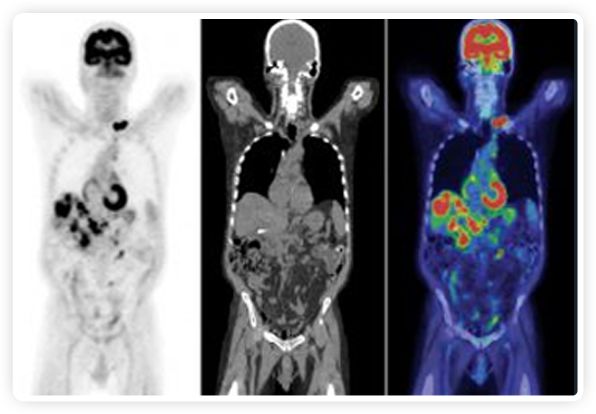

提起放療設備的引導系統(tǒng),大家通常會想到結(jié)構(gòu)性成像的CT或核磁。但你有沒有想過用功能性成像來引導放療呢?美國的一家醫(yī)療器械公司從2011年就致力于研究開發(fā)用PET提供生物學指導放射治療的設備BgRT。BgRT能實時利用癌癥的生物學特征作為信號指導治療全身腫瘤。

到目前為止,放射腫瘤學中(使用的圖像主要是結(jié)構(gòu)性的,而PET圖像可以提供生物學信息。通過使用注射示蹤劑,例如18-FDG,PET可以描繪腫瘤的代謝活性,使其“點亮”。(FDG是用于可視化癌癥代謝的最廣泛使用的示蹤劑。與正常組織相比,腫瘤細胞保留更高水平的FDG。)不同的PET示蹤劑可以識別腫瘤的不同生物學特征,例如特定生物標志物抗原(例如,PSMA)或甚至探測免疫系統(tǒng)本身(例如,PDL1表達或活化的T細胞)。

RefleXion將PET成像與立體定向放射治療相結(jié)合。在注射示蹤劑后,RefleXion的技術(shù)基于示蹤劑信號實時地在一個或多個目標上引導治療性X射線。使用這種專有方法,RefleXion的平臺有可能比現(xiàn)有系統(tǒng)向癌癥病變提供更高劑量的輻射,并改善周圍健康組織的保護。

為了避免PET長圖像采集時間,RefleXion開發(fā)了一項專利技術(shù)使用重合的PET光子對來指導放射治療束,因為實時檢測發(fā)射的光子,為生物指導提供了一種時間有效的方法。